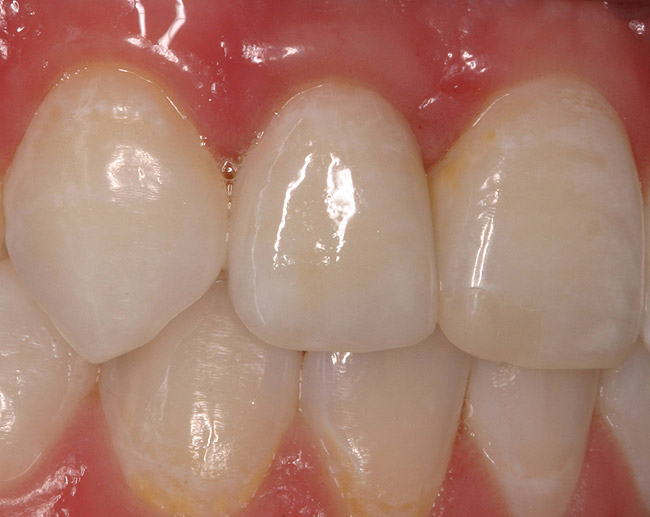

Figure 6d Completed treatment: revised RCT, zirconium post/pressed ceramic core cemented with Panavia 21¬Æ Resin Cement (Kuraray Dental). All-ceramic full-coverage crown cemented with Kerr NX3 Nexus¬Æ Third Generation Dual Cure Resin cement. Implant therapy not indicated.

Figure 6d

Figure 6e  Completed treatment: revised RCT, zirconium post/pressed ceramic core cemented with Panavia 21¬Æ Resin Cement (Kuraray Dental). All-ceramic full-coverage crown cemented with Kerr NX3 Nexus¬Æ Third Generation Dual Cure Resin cement. Implant therapy not indicated.

Figure 6e

Figure 6f  Completed treatment: revised RCT, zirconium post/pressed ceramic core cemented with Panavia 21¬Æ Resin Cement (Kuraray Dental). All-ceramic full-coverage crown cemented with Kerr NX3 Nexus¬Æ Third Generation Dual Cure Resin cement. Implant therapy not indicated.

Figure 6f